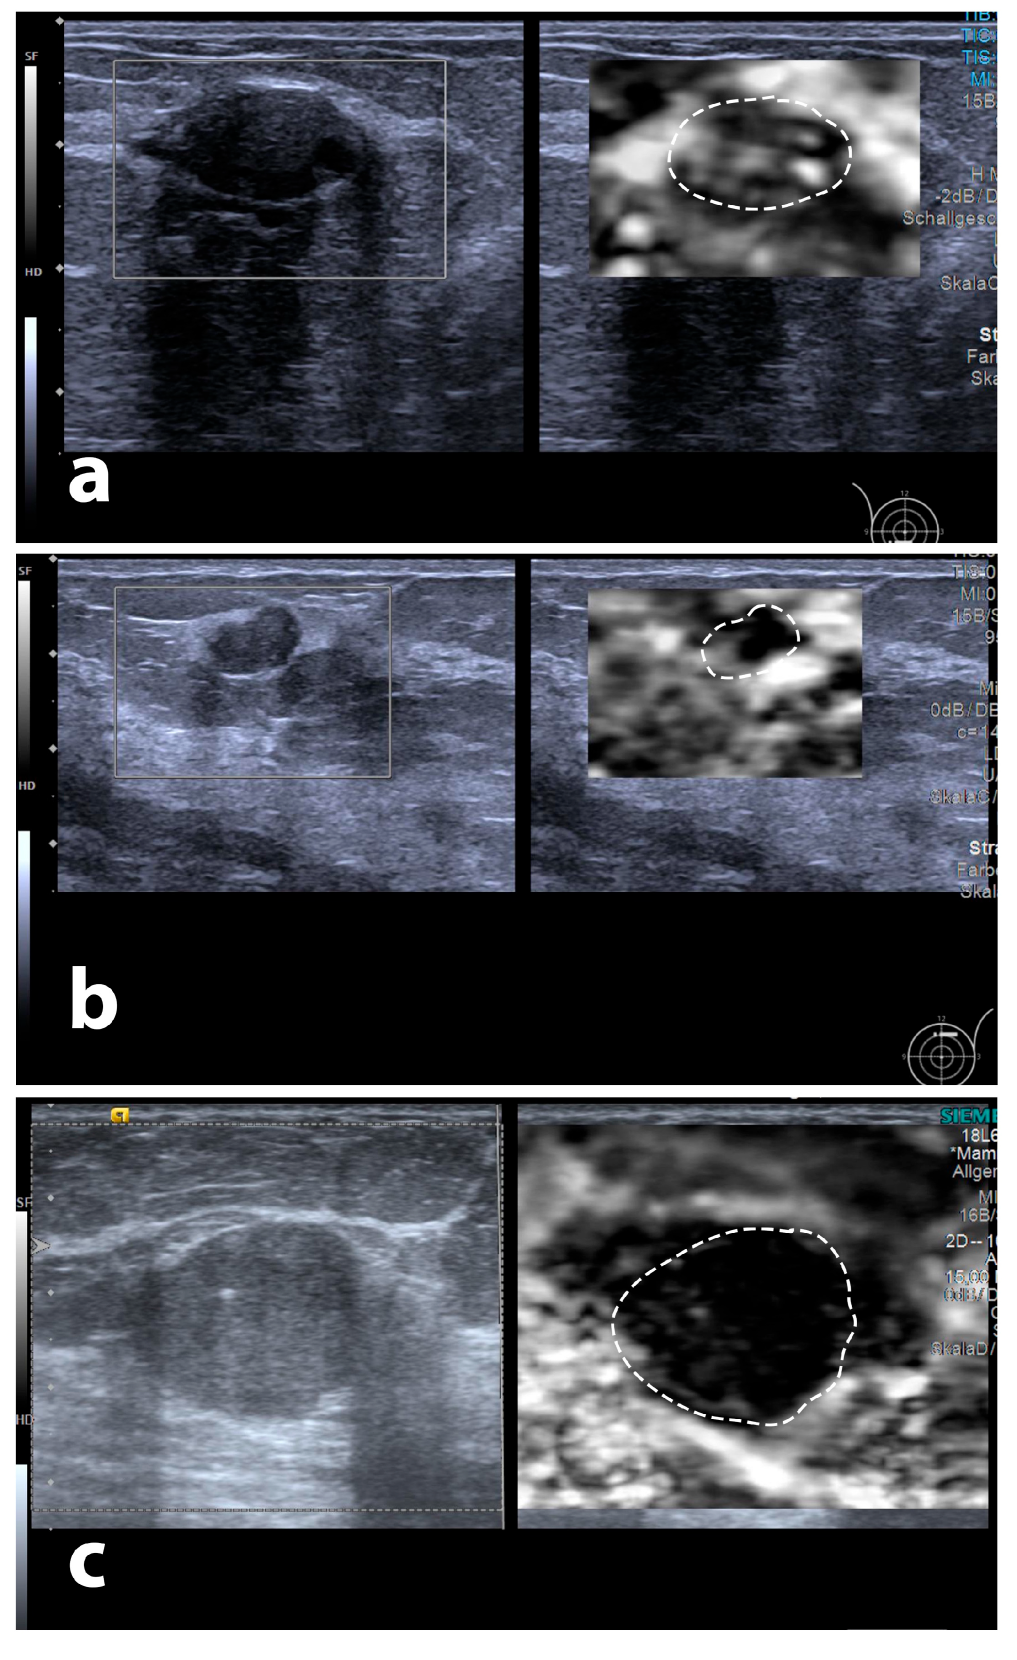

Figure 7.

Examples for differing degrees of maximum peritumoural halo depth, three tumours with B-mode echotexture and surface: (a) BI-RADS 2 lesion (fibrous-cystic mastopathy) in a 45-year-old patient, (b) BI-RADS 3 tumour (atypical ductal hyperplasia) in a 21-year-old patient, and (c) BI-RADS 5 tumour (NST G2) in a 58-year-old patient. Dotted contours represent tumour outlines transferred onto elastography images.